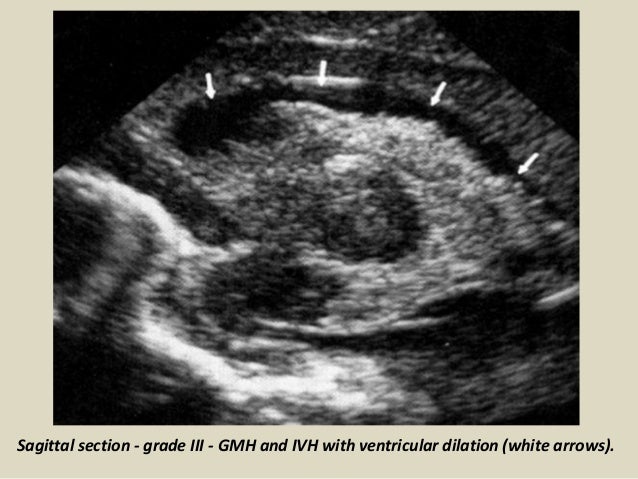

19. 19. Sagittal section - grade III - GMH and IVH with ventricular dilation (white arrows).